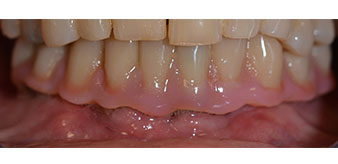

L'empreinte et l'enregistrement de l'occlusion ont ensuite été effectués afin que le prothésiste dentaire puisse commencer à réaliser la restauration provisoire. Celle-ci a été vissée le jour même (Fig. 17 et 18).

Après ostéointégration, l'empreinte finale des implants a été effectuée et la prothèse finale a été fabriquée en conséquence (Fig. 19 et 20). À cette étape, le praticien et le patient ont pu décider ensemble d'utiliser une facette dentaire en céramique ou en acrylique et une armature en zircone ou en métal. Dans ce cas, l'équipe du Dr Pascu a opté pour une facette dentaire en acrylique en raison du pronostic incertain de la denture maxillaire et du fait que la dent 24 est extrusée. Ce type de facette est plus facile à ajuster et peut donc être modifiée selon la nouvelle situation maxillaire.